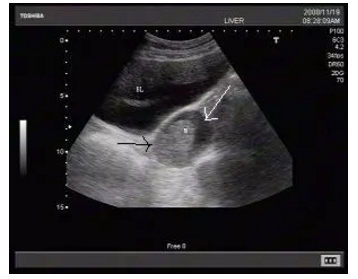

2、低回声、无回声、

边界清楚、边界不清

超声报告里通常会形容结节是“低回声”或“无回声”。在超声的黑白图像上,各种不同性质的“结节”自然有的黑一些(低回声),有的更黑一些(无回声)。“边界清楚”或“边界不清”则是形容这些“结节”在图像上是否清晰可辨。不能说“边界不清”就是恶性的,或者“边界清楚”就是良性,这还需要医师具体分析。